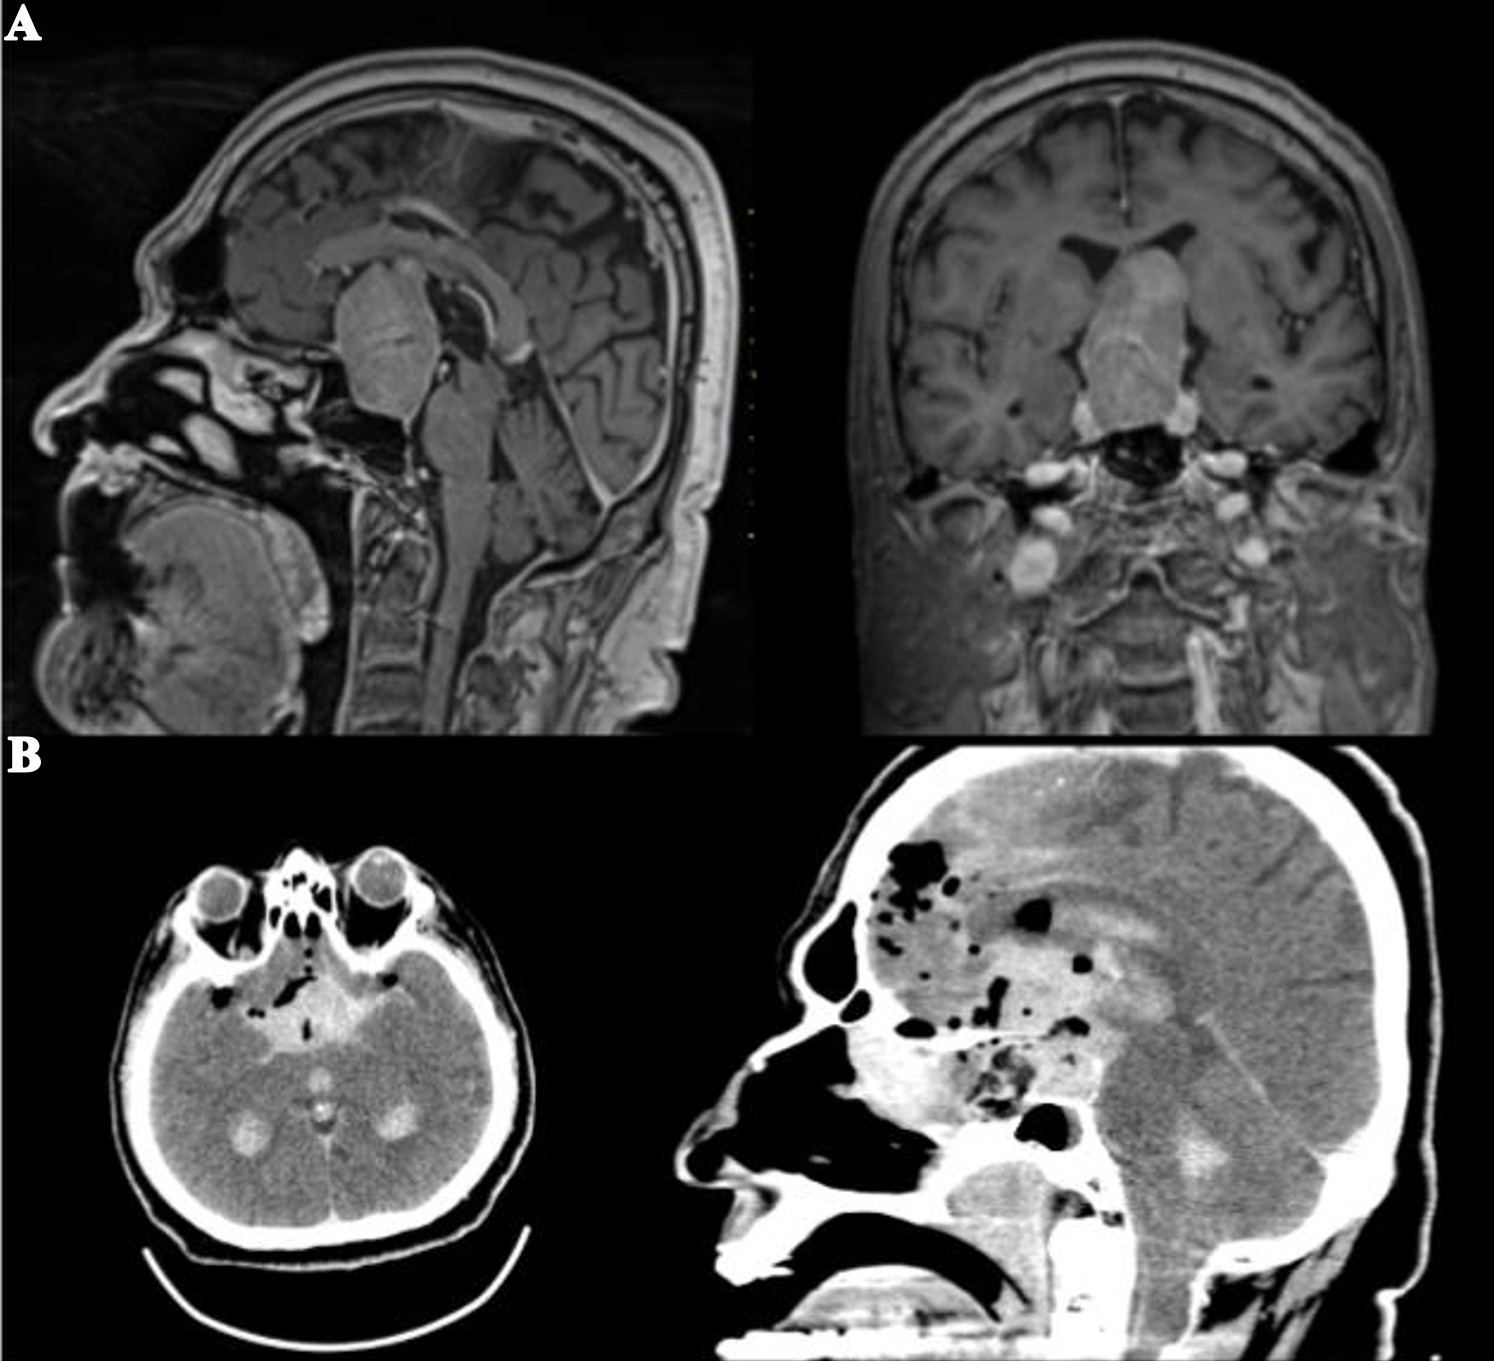

Bu çalışmaya toplam 204 hasta dahil edildi. Hastaların yaş ortalaması 47,3 ± 13,9 yıl olup, geniş bir yaş dağılımı mevcuttu. Olguların 120’si (%58,8) kadın, 84’ü (%41,2) erkekti. Patolojik değerlendirmede en sık saptanan tümör tipi Cushing hastalığı (%20,1) idi. Bunu sırasıyla non-fonksiyonel hipofiz adenomları (%19,6), FSH-LH sekresyonlu adenomlar (%16,7) ve akromegali (%14,2) izledi. Daha az sıklıkta izlenen patolojiler arasında izole hormon salgılayan adenomlar ve nadir hipofizer lezyonlar yer aldı. Postoperatif dönemde diabetes insipidus gelişmesi nedeniyle 70 hastada (%34,3) desmopressin tedavisi gerekli oldu. Bu hastaların 4’ünde (%5,7) uzun dönem takiplerinde desmopressin ihtiyacının devam etmesi nedeniyle kalıcı diabetes insipidus olarak tanımlanmıştır. Geçici diabetes insipidus, postoperatif erken dönemde sık gözlenen komplikasyonlardan biri olarak kaydedildi. Rinore, 30 hastada (%14,7) izlenmiş olup, bu olguların 22’si klinik ve radyolojik olarak BOS fistülü ile uyumlu bulunarak reoperasyona alındı. Reoperasyon sırasında uygulanan onarım yöntemleri heterojenlik göstermekteydi. Bu olguların 14’ünde yağ grefti ile birlikte lomber drenaj, 7’sinde yalnız yağ grefti, 3’ünde yalnız lomber drenaj kullanıldı (Şekil 1). Beş olguda herhangi bir greft veya drenaj uygulanmazken, bir olguda otojen kemik grefti tercih edildi. Rezidüel adenom saptanan hastaların tedavi yaklaşımları incelendiğinde, 4 hastaya ek endoskopik cerrahi, 6 hastaya ise transkranyal cerrahi uygulandığı görüldü. Bu hastalar, rezidüel lezyonun lokalizasyonu ve yayılım özelliklerine göre değerlendirilerek tedavi edildi. Postoperatif hematom, 8 hastada (%3,9) izlendi (Şekil 2). Bu olguların iki tanesinde vasküler yaralanma gelişmesi üzerine endovasküler tedavi uygulanması gerekti. Diğer postoperatif komplikasyonlar arasında epistaksis (n=4, %2), menenjit (n=5, %2,4) ve hidrosefali (n=2, %1) yer aldı. Tüm olgular değerlendirildiğinde mortalite oranı %0,5 olup, bir hasta postoperatif dönemde kaybedildi. Demografik özellikler, patolojik tanı dağılımı ve postoperatif komplikasyonlara ait bulgular Tablo 1’de özetlenmiştir.